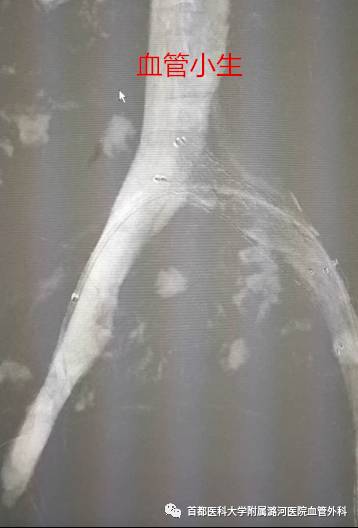

(手术中解剖)图片来自网络

尸体解剖